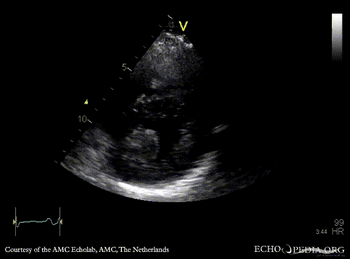

Case 142